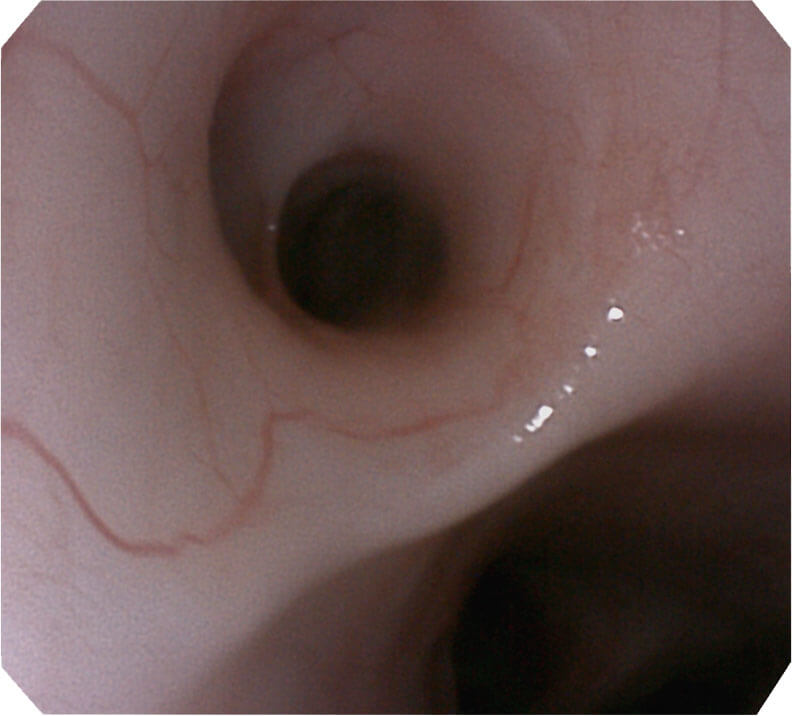

120°视场角,满足更大视野范围的观察。配合 VIST 染色,助力呼吸系统疾病的诊断。

光电复合染色成像技术(VIST)是一种光学滤波和数字滤波相结合的染色成像技术,摒弃了滤光转轮而直接采用光谱组合的方案,加入了血红蛋白吸收高峰与次高峰的蓝紫光和绿光光谱,更有利于黏膜血管吸收,突显浅表层血管和中层血管的对比度,因而具备更高的图像对比度,有助于观察微细结构变化及病灶边界的观察。